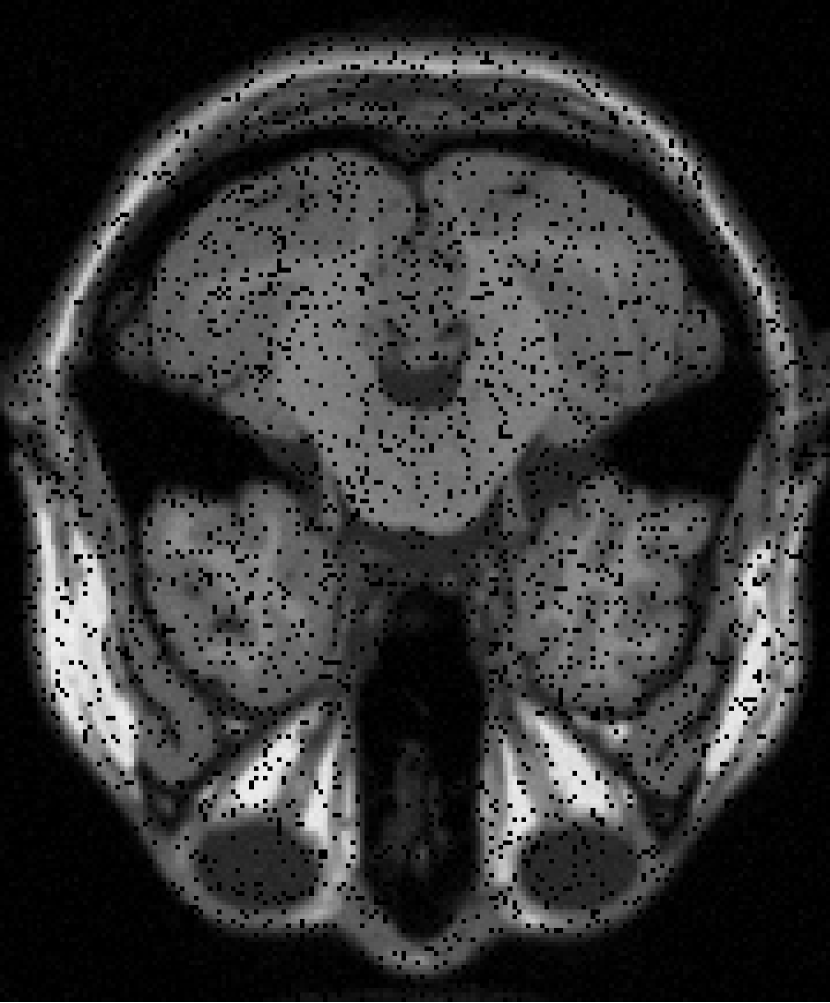

The resolution of the MRI volume dataset333http://graphics.stanford.edu/data/voldata/ is of size with 181 slices and we selected the 38th slice and the 88th slice for the experiment. We consider the case where entries are missing at random by sampling ratio . The GMM noise are set at .

From Figure 12 and Histogram 14, we can see that the effect of FPCA and SVT to restore images is very poor. The effect of VBMFL1 algorithm to restore images is good, but the running time is relatively long. SPG algorithm to restore the image effect and good running time is short. In summary, the SPG algorithm has the best recovery effect.